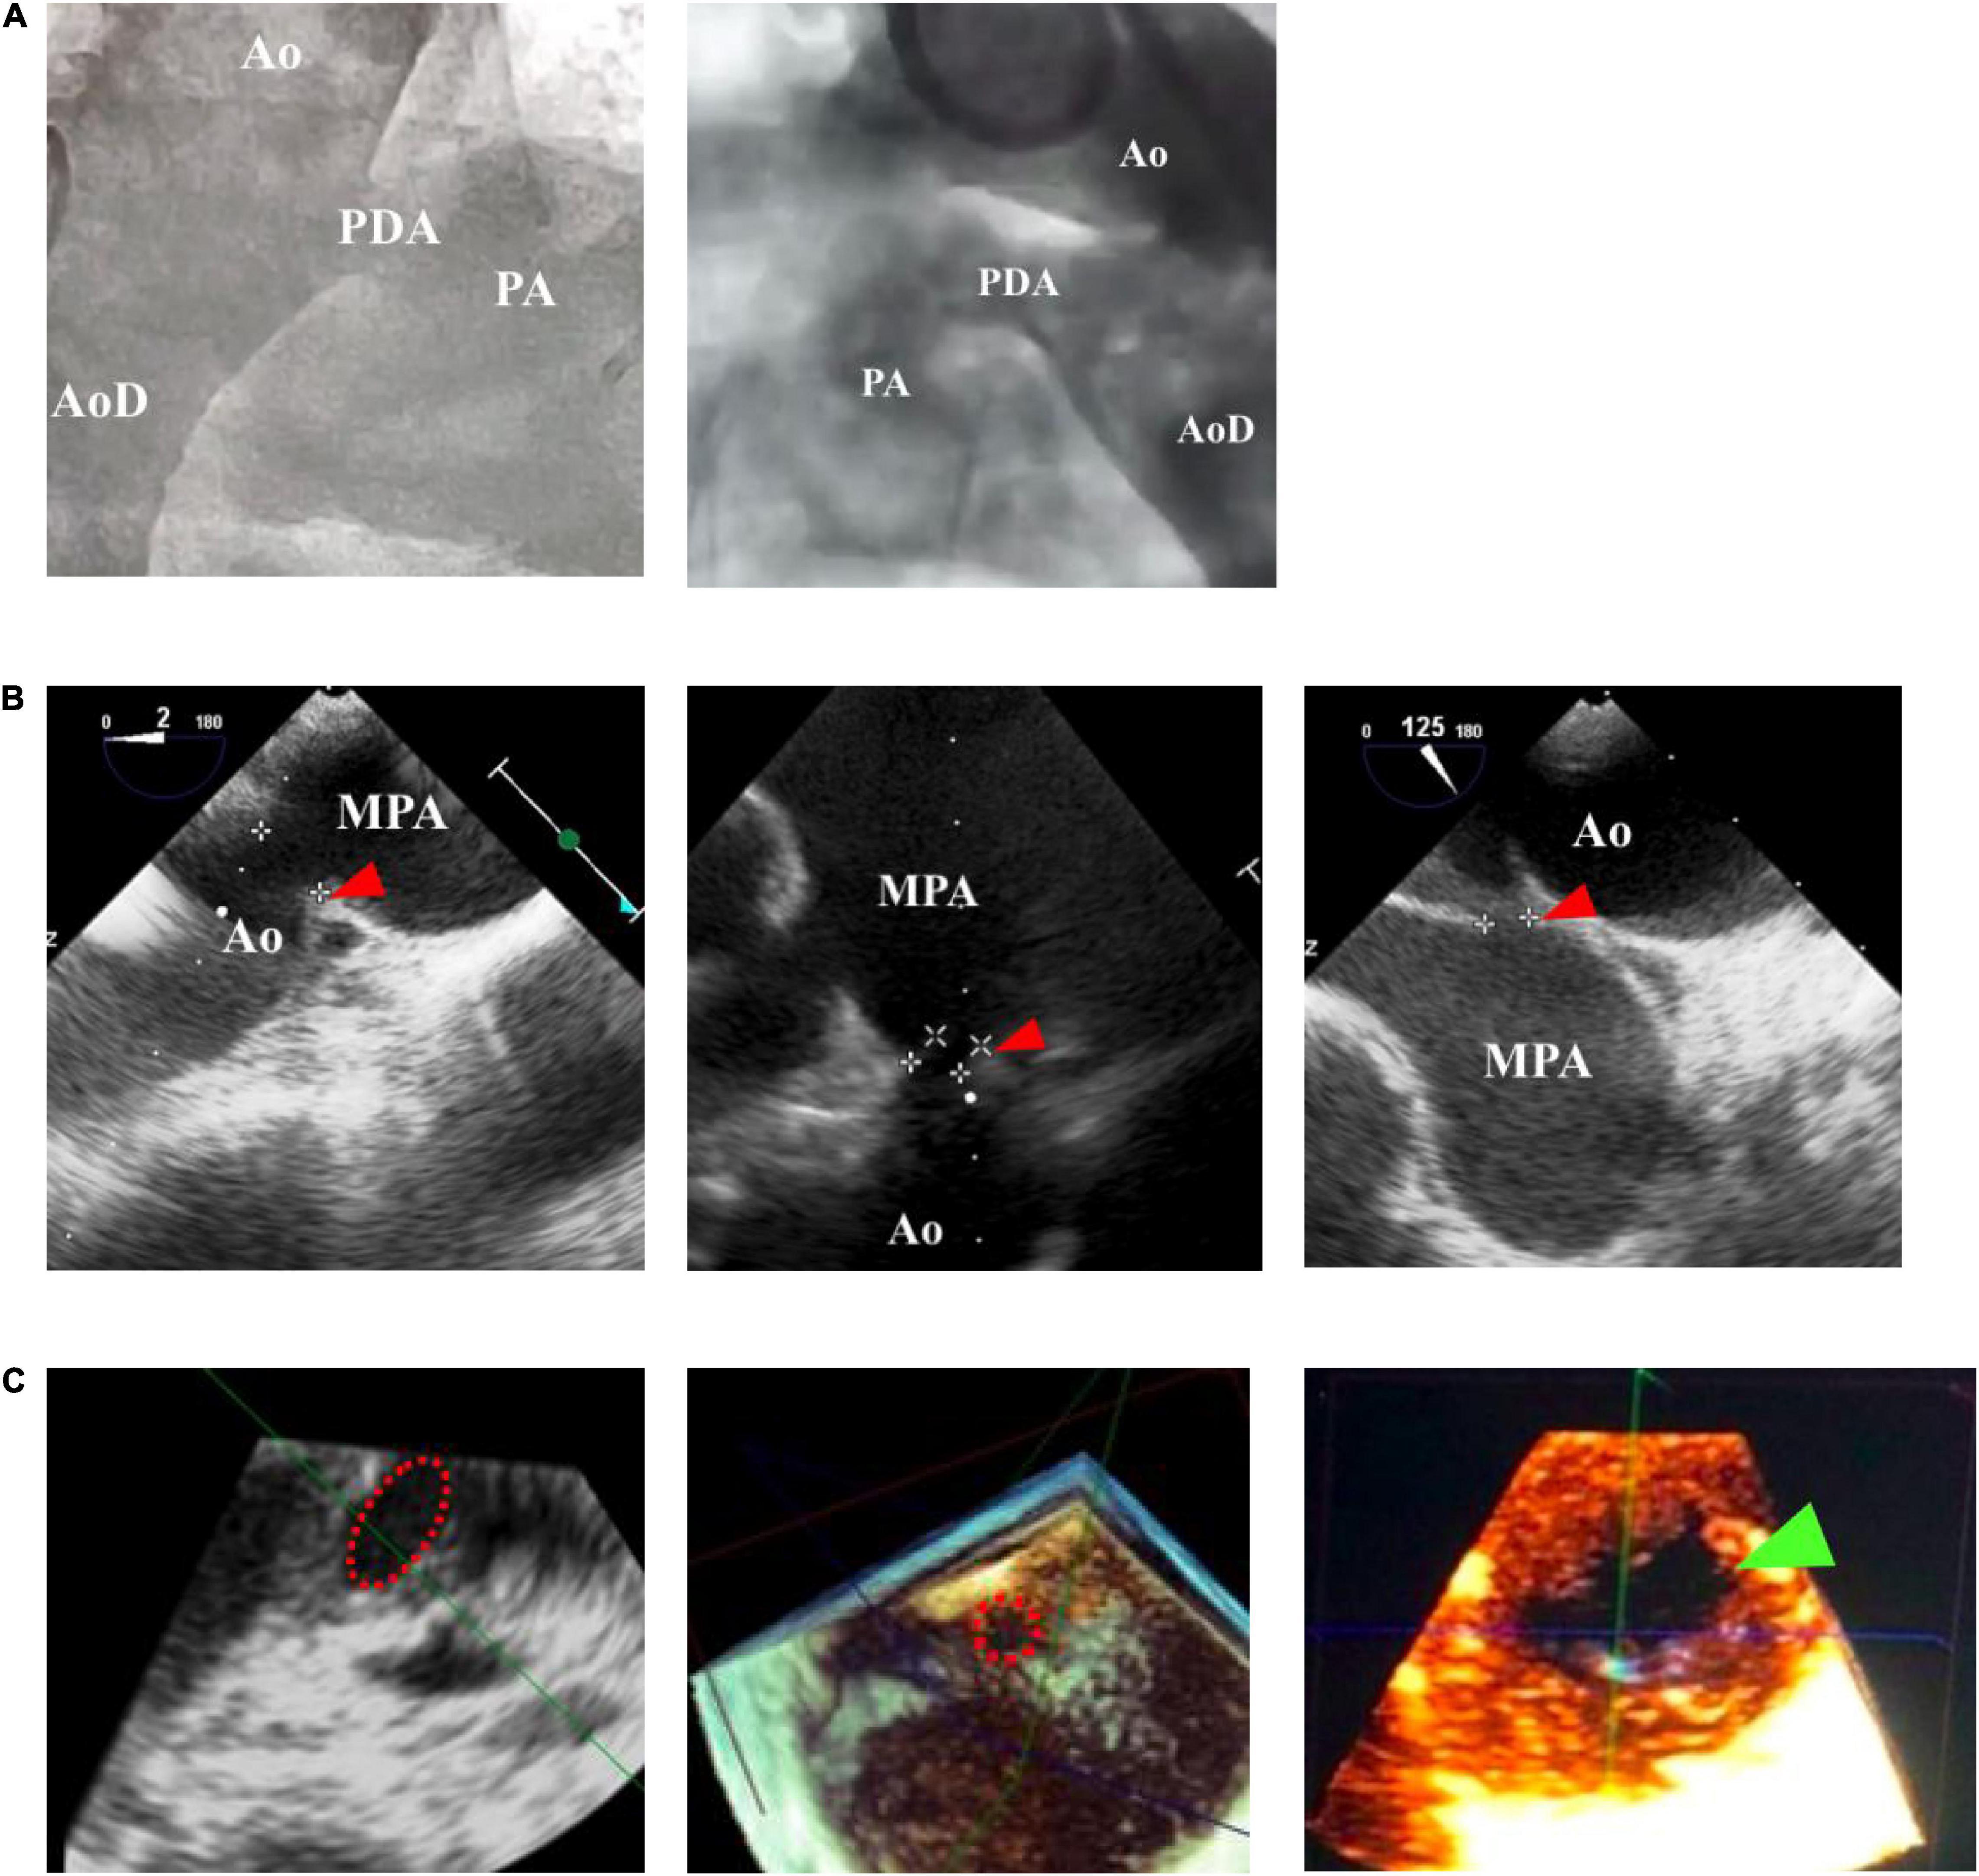

FIGURE 1

www.frontiersin.org

Figure 1. Comparison of patent ductus arteriosus (PDA) size and morphology measurements using fluoroscopy and echocardiography guidance. (A) Fluoroscopy can only provide a 2-dimensional image, whereas (B) transthoracic echocardiography (TTE) and transesophageal echocardiography (TEE) can provide a 3-dimensional structure as shown by the red arrowhead. (C) Cross-sectional PDA morphology measured by using transesophageal echocardiography (TEE), indicated by the dotted red circle. Green arrowhead showed oval-shaped PDA. Ao, aorta; AoD, descending aorta; MPA, main pulmonary artery; PA, pulmonary artery.